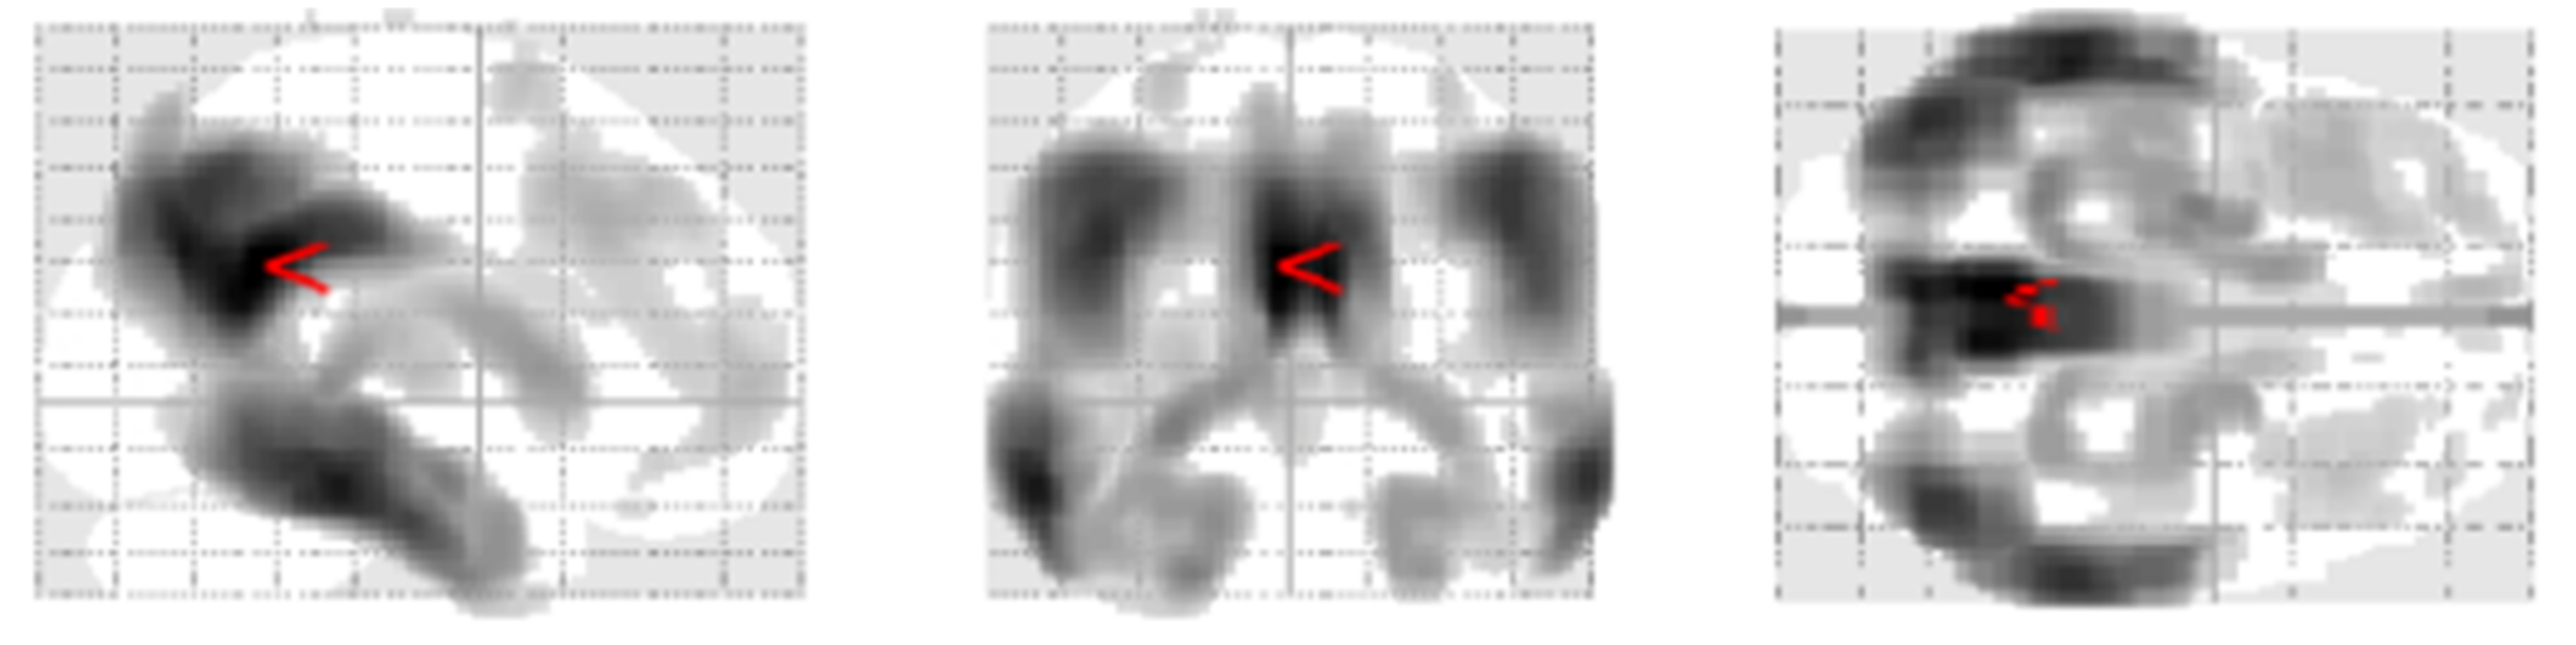

- Minoshima, S.; Frey, K.A.; Koeppe, R.A.; Foster, N.L.; Kuhl, D.E. A diagnostic approach in Alzheimer’s disease using three-dimensional stereotactic surface projections of fluorine-18-FDG PET. J. Nucl. Med. 1995, 36, 1238–1248. [Google Scholar]

- Ishii, K.; Willoch, F.; Minoshima, S.; Drzezga, A.; Ficaro, E.P.; Cross, D.J.; E Kuhl, D.; Schwaiger, M. Statistical brain mapping of 18F-FDG PET in Alzheimer’s disease: Validation of anatomic standardization for atrophied brains. J. Nucl. Med. 2001, 42, 548–557. [Google Scholar]

- Burdette, J.H.; Minoshima, S.; Vander Borght, T.; Tran, D.D.; Kuhl, D.E. Alzheimer disease: Improved visual interpretation of PET images by using three-dimensional stereotaxic surface projections. Radiology 1996, 198, 837–843. [Google Scholar] [CrossRef] [PubMed]

- Thientunyakit, T.; Sethanandha, C.; Muangpaisan, W.; Minoshima, S. 3D-SSP analysis for amyloid brain PET imaging using 18F-florbetapir in patients with Alzheimer’s dementia and mild cognitive impairment. Med. J. Malays. 2021, 76, 493–501. [Google Scholar]